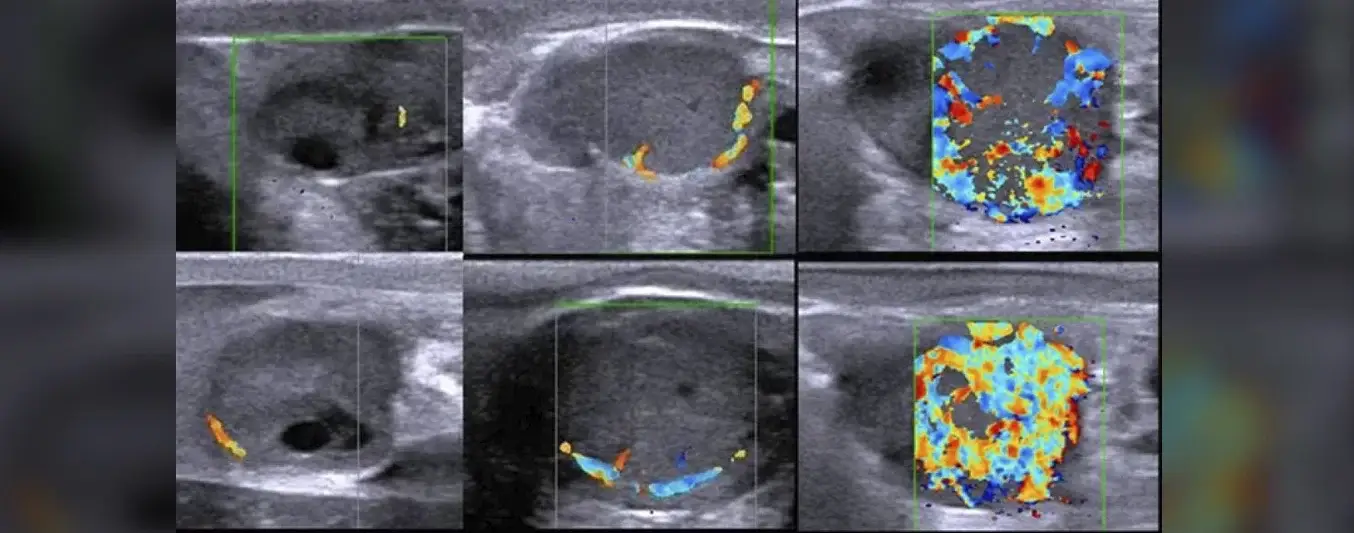

El principio detrás del Doppler es sencillo porque traduce los cambios de frecuencia del sonido emitido por el flujo sanguíneo en imágenes codificadas por color.

A través de esta lectura, es posible interpretar la perfusión sanguínea en el cuerpo lúteo. Si hay una baja perfusión, es señal de que el cuerpo lúteo no está activo, lo que implica una baja de progesterona en sangre y, por ende, una vaca no gestante.

El Doppler color y el Doppler pulsado son dos de las modalidades más utilizadas en veterinaria. El primero permite visualizar el flujo sanguíneo en tiempo real, detectando dirección y velocidad, mientras que el segundo mide con mayor detalle la intensidad de ese flujo.

Ambas herramientas son claves para evaluar la funcionalidad del cuerpo lúteo, estructura responsable de la producción de progesterona y del mantenimiento de la gestación.